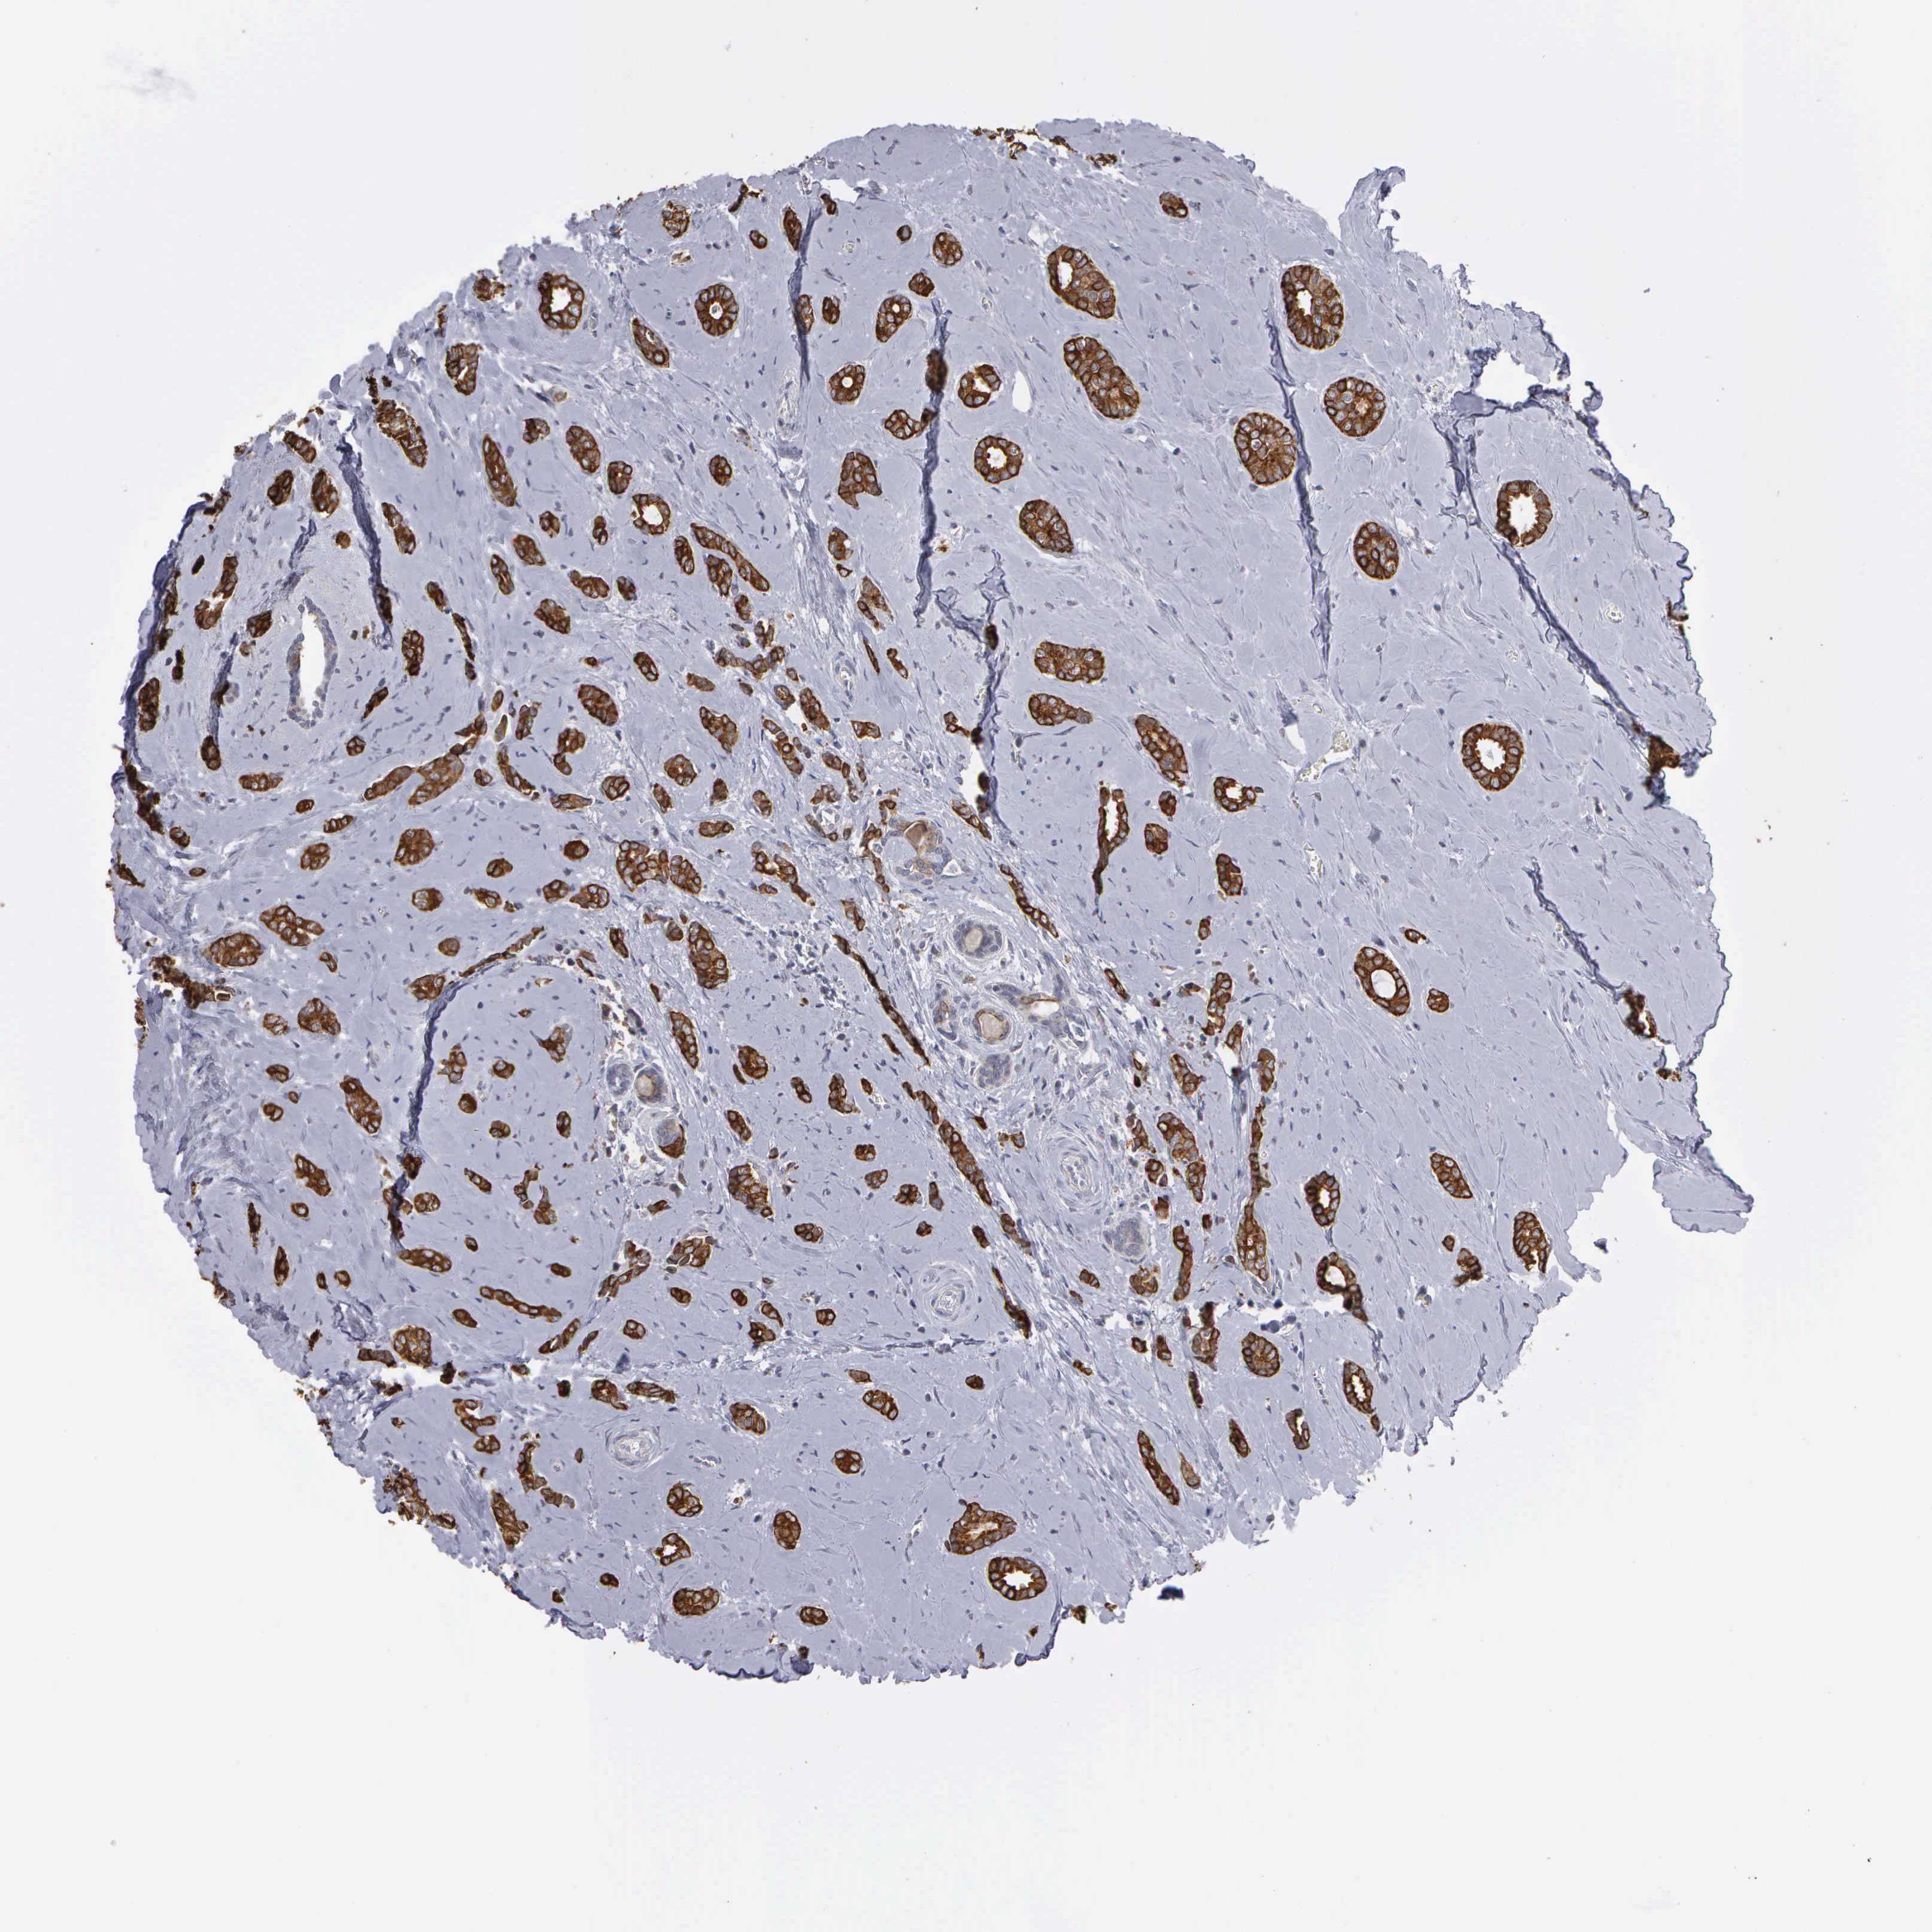

BRCA TCGA BRCA VALIDATION PROTEIN EXPRESSION

Breast cancer

Human cancer